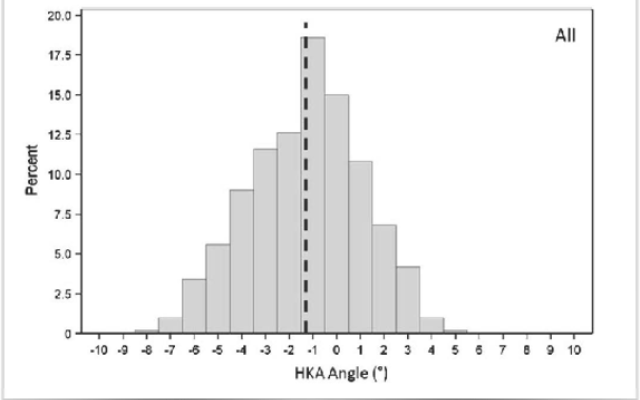

OLIVIA GRACE-CURRAN, Townsville Bulletin March 20, 2018 12:00am SMOKERS are being urged to consider others and heed signs discouraging smoking near public and private health facilities. Smoking is prohibited within 5m of all public and private health facilities in Queensland. A Townsville orthopaedic surgeon is hoping local health providers consider driving an initiative to enforce the...Computer Navigation is for the Outliers!!!!!!

Posted in Dr Kaushik Hazratwala Blogs on Saturday, 27 January 2018 by Kaushik Hazratwala

By Dr Kaushik Hazratwala, Orthopaedic Surgeon, Director – Orthopaedic Research Institute of Qld Director – Townsville Lower Limb Clinic Finally, after 15 yrs. this Korean group has proven that Computer Navigation will not improve patient outcome in all comers. The proponents of conventional Knee replacements will rejoice in this publication and uncork expensive French...Platelet Rich Plasma (PRP) - Latest Evidence or Lack of !!!